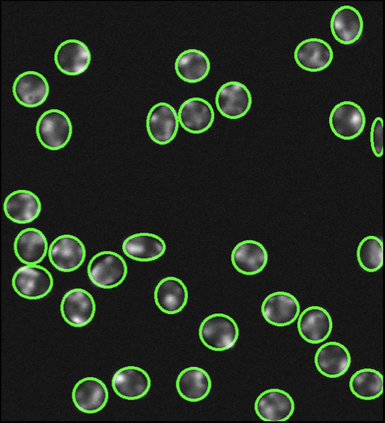

Cell detection in microscopy images is important to study how cells move and interact with their environment. Most recent deep learning-based methods for cell detection use convolutional neural networks (CNNs). However, inspired by the success in other computer vision applications, vision transformers (ViTs) are also used for this purpose. We propose a novel hybrid CNN-ViT model for cell detection in microscopy images to exploit the advantages of both types of deep learning models. We employ an efficient CNN, that was pre-trained on the ImageNet dataset, to extract image features and utilize transfer learning to reduce the amount of required training data. Extracted image features are further processed by a combination of convolutional and transformer layers, so that the convolutional layers can focus on local information and the transformer layers on global information. Our centroid-based cell detection method represents cells as ellipses and is end-to-end trainable. Furthermore, we show that our proposed model can outperform fully convolutional one-stage detectors on four different 2D microscopy datasets. Code is available at: https://github.com/roydenwa/cell-centroid-former